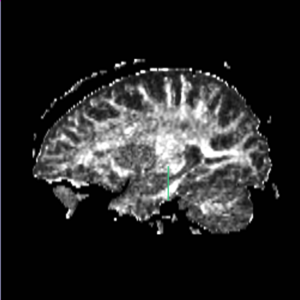

Boundaries for the ROI's, mainly using FA maps & color by orientation, followed by the color coding of the labelmaps.

unc - Uncinate FasciculusFind the most prominant (central) slice of the fornix according to saggital view. Go one slice anterior to the most anterior point of the fornix and draw Left and Right ROI 1 and ROI 2.